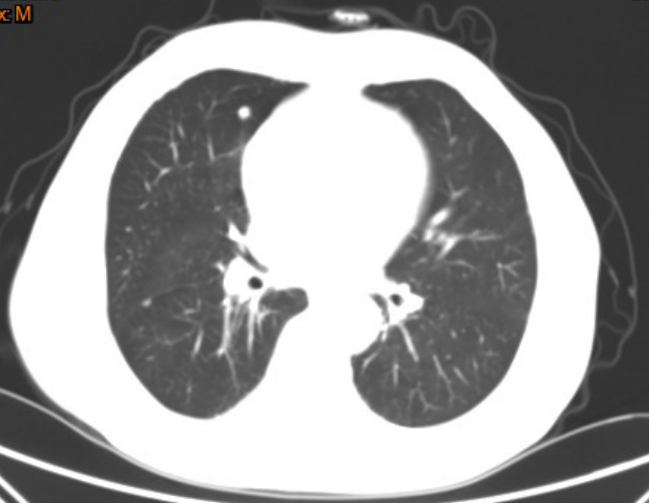

影像学检查

左肺上叶结节影,边界光整,大小约11*12mm,两肺见多发大小不等结节灶。

手术所见:胸腔镜下行肺叶部分(左肺上叶结节)切除术,术中探查见肿块约2*1.5*1cm大小,位于前段与舌段交界处。